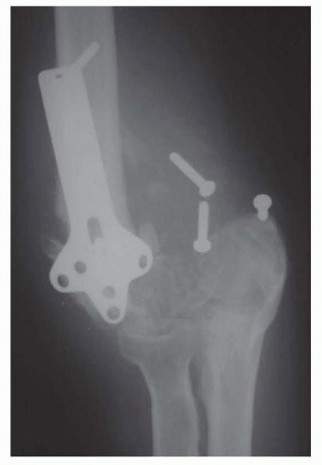

30 MIN READ Primary Repair and Nerve Grafting following Complete Nerve Transection in the Hand, Wrist, and Forearm يناير 2023 Read More